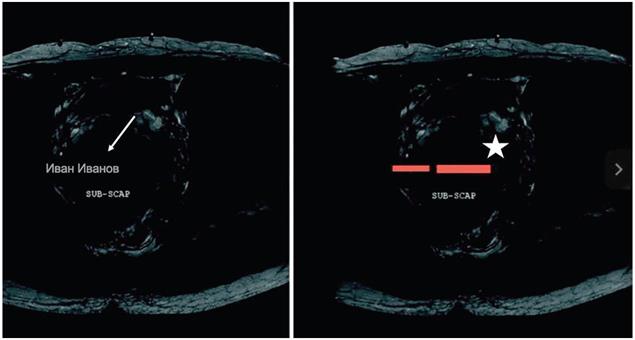

Для обезличивания данных областей выполняют наложение бинарной маски (маскирование), которая, например, имеет значения 0 - для областей, содержащих персональных данные, и 1 - для области, выделенной методом OCR как содержащей персональные данные. Пример осуществления данного метода приведен на рисунке 4.

Рисунок 4 - Пример применения наложения маски на области с персональными данными: слева - исходное изображение, стрелкой обозначено положение имени пациента; справа - обезличенное изображение, звездой обозначено положение участков изображения с наложением маски (см. [13])